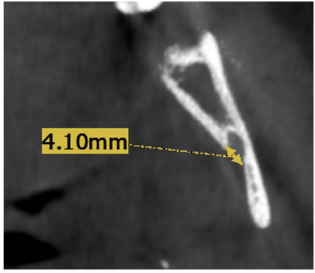

- MF height: In the sagittal view, the axial plane was adjusted on the buccal cusp tip of the mandibular first premolar and mesiobuccal cusp tip of the mandibular first molar (Fig. 2A), then from the coronal view, a line was drawn from the inferior border of MF to the axial plane (Fig. 2B).

A) Identification of occlusal plane on the sagittal view. B) Measurment of height from occlusal plane to lower border of MF on the coronal view.